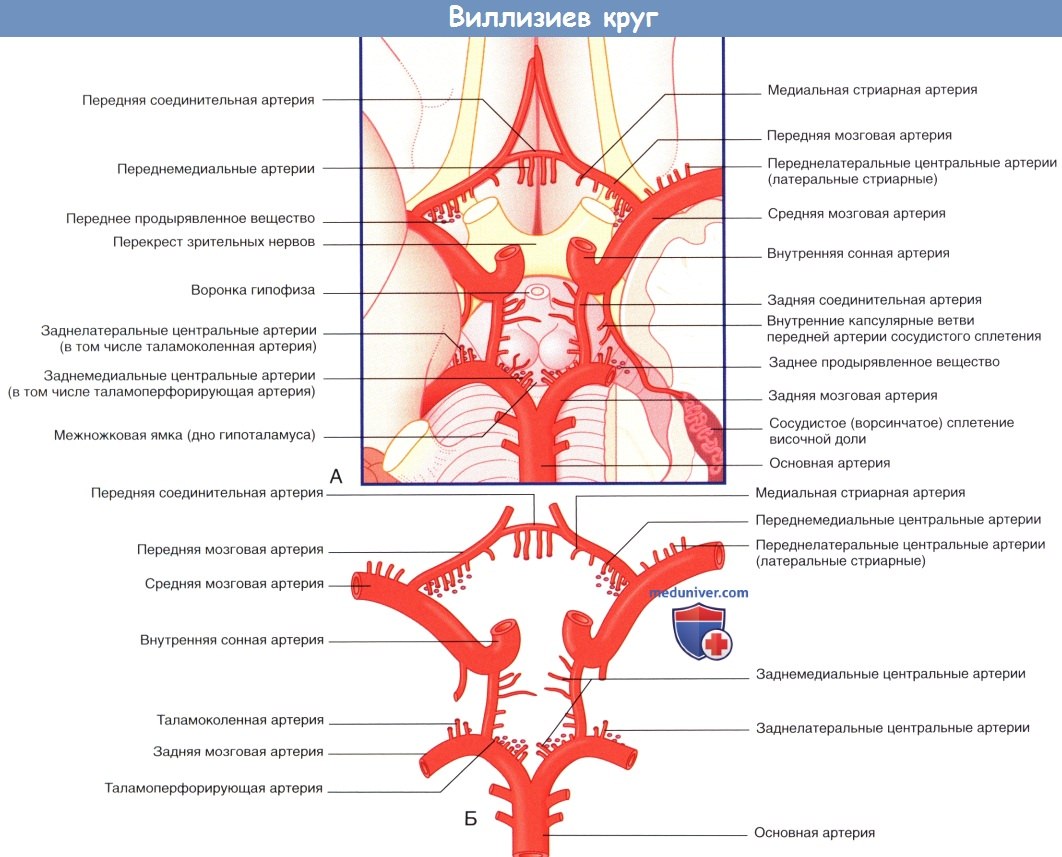

Анатомия: Задняя соединительная артерия мозга